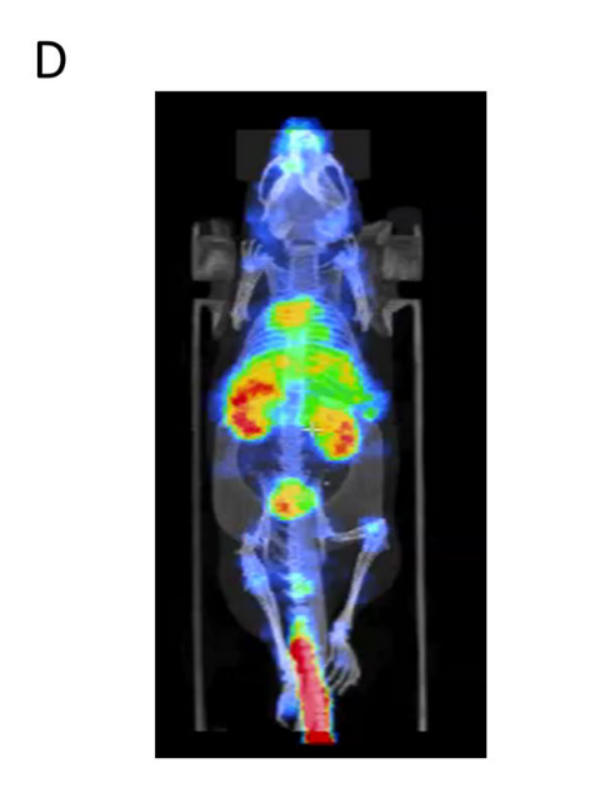

采用

NanoScan SPECT/CT

設備進行 EVs 體內分布成像,將 ¹¹¹In 標記的 EVs 通過尾靜脈注射入小鼠體內,2 小時后采集圖像。掃描時采用適宜的準直器和掃描參數,獲取全身多平面 SPECT-CT 圖像,利用廠家提供的 Nucline 軟件進行圖像重建與顯示,所有圖像格式化為 Analyze 格式并進行多平面重建,以清晰呈現 EVs 在各器官的富集情況。

原文Fig. 3D:SPECT/CT 成像顯示的 EVs 體內分布圖

分子影像設備的結果

SPECT/CT 成像

清晰顯示,尾靜脈注射的 EVs 可靶向歸巢至小鼠多個內臟器官,證實其體內分布的廣泛性,排除了單一器官局限作用的可能。該設備通過精準的成像與重建技術,直觀反映了 EVs 的體內靶向特性,為后續(xù)驗證 EVs 及 miRNA 的全身治療效果提供了關鍵的影像學證據,充分體現了其在生物標志物體內分布研究中的精準性和可靠性。